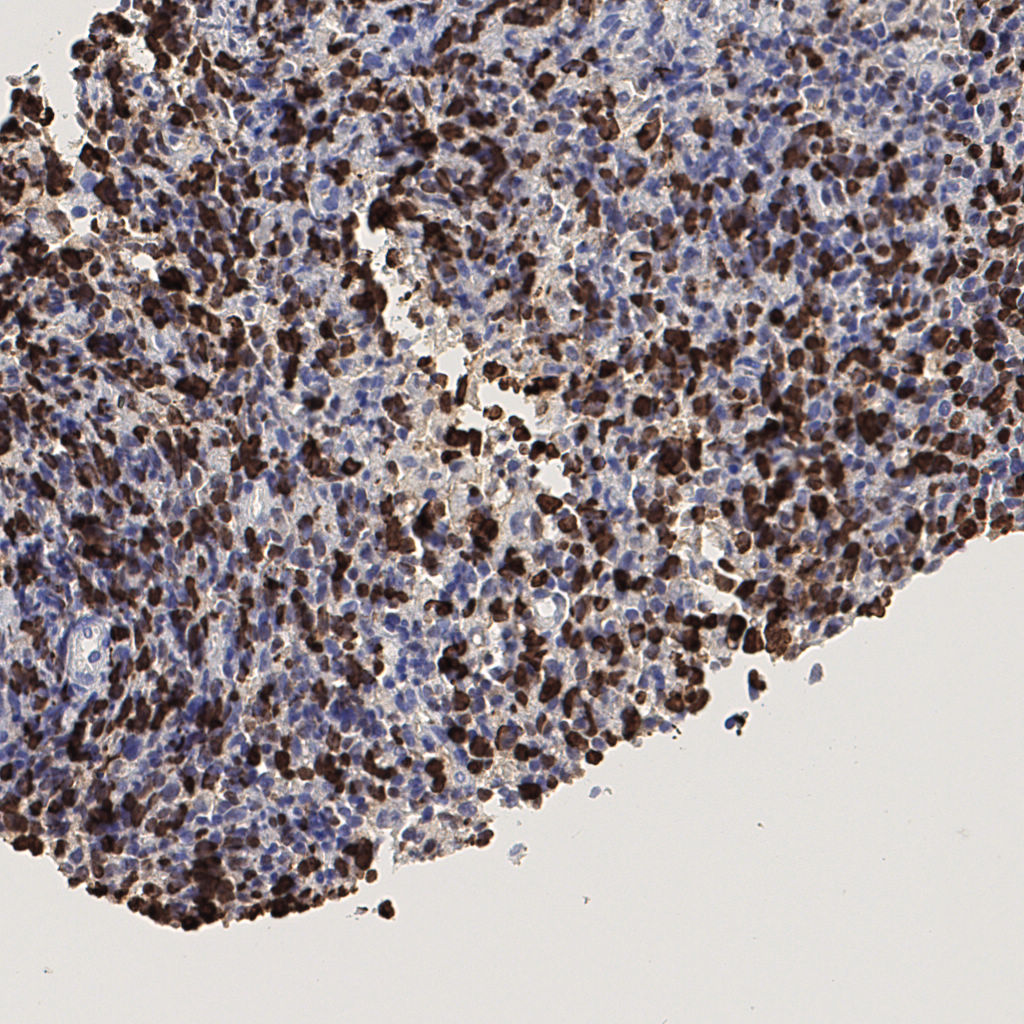

7.85%

Ki67 指数

阴 1104 阳 94

切片统计

总切片 1953

有效 288

已标记 288

有效率 15%